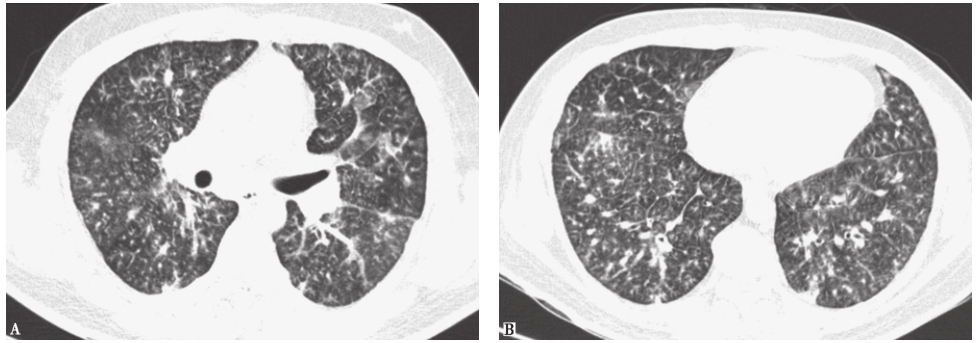

10天前胸部CT见双肺呈随机分布的弥漫性粟粒样小结节影(图2)。

图2 10天前胸部CT表现